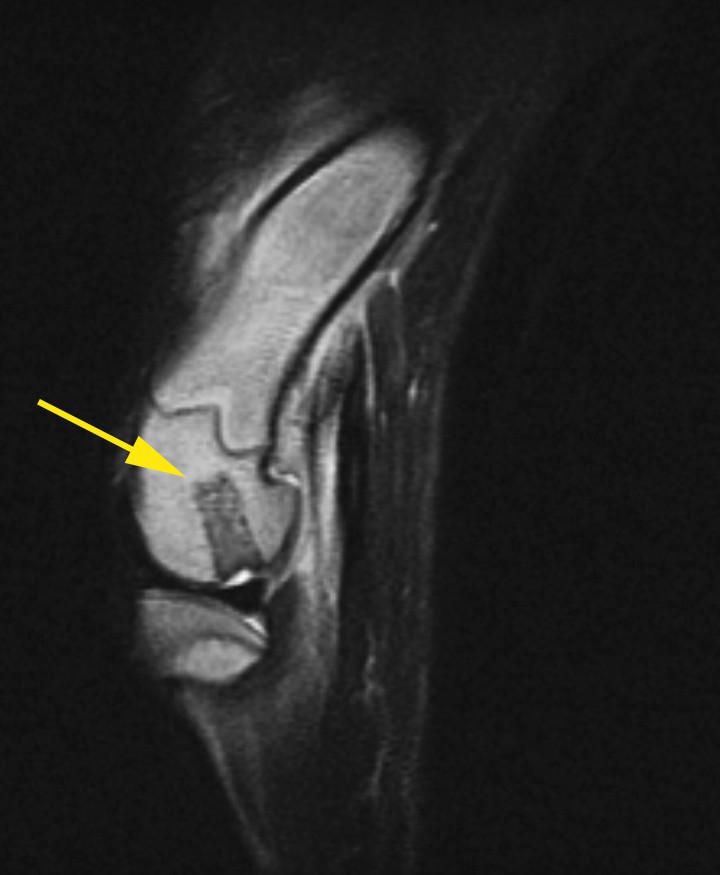

En la revisión, después de 6 semanas desde la intervención y con dos infiltraciones de PRP intraarticulares realizadas, se llevó a cabo una resonancia magnética en la cual se observó que el autoinjerto se estaba osteointegrando adecuadamente (Fig. 6).[ Gonzalo-Orden JM, Altónaga JR, Millán L, Gonzalo JM, Orden MA. Magnetic resonance imaging in 50 dogs with stifle lameness. Eur J Comp Anim Pract, 2001, 11:115-118. [PubMed] ]

<p>Imagen de resonancia magnética en T2 y corte sagital del cóndilo femoral izquierdo a las 6 semanas de la realización del procedimiento quirúrgico. Se puede observar una cierta osteointegración, sobre todo en la zona de la base del cilindro a nivel del hueso subcondral (flecha amarilla).</p>

Imagen de resonancia magnética en T2 y corte sagital del cóndilo femoral izquierdo a las 6 semanas de la realización del procedimiento quirúrgico. Se puede observar una cierta osteointegración, sobre todo en la zona de la base del cilindro a nivel del hueso subcondral (flecha amarilla).